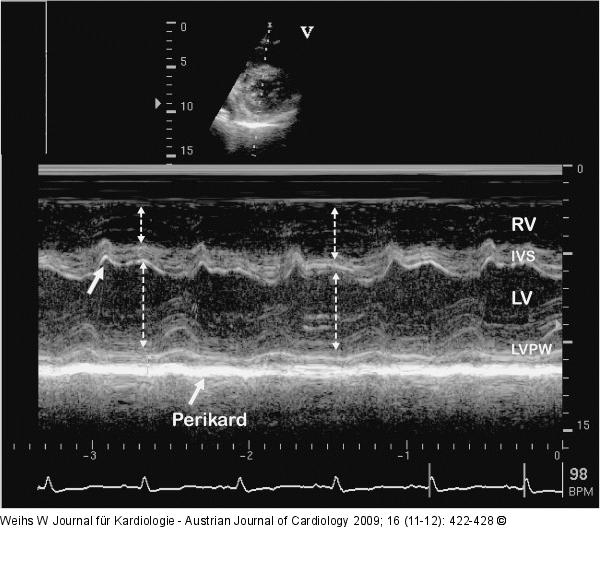

Abbildung 3: PC M-Mode des linken Ventrikels bei einem Patienten mit PC. Das Perikard ist mit 5 mm deutlich verdickt. Charakteristisch sind die abnorme Septumbewegung (Pfeil), die diastolische Abplattung der Hinterwand und die respiratorischen Schwankungen der Durchmesser des linken und rechten Ventrikels (unterbrochene Pfeile). |